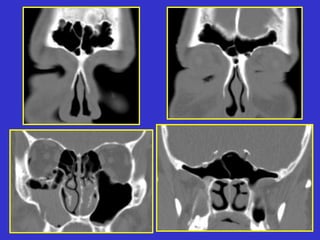

Este documento describe las diferentes proyecciones radiográficas utilizadas para examinar los senos paranasales, incluyendo las proyecciones básicas de Caldwell, Waters lateral y las proyecciones especiales como Hirtz y Waters mentonasal. También describe las diferentes estructuras anatómicas que componen el complejo ostiomeatal anterior y posterior de los senos paranasales.